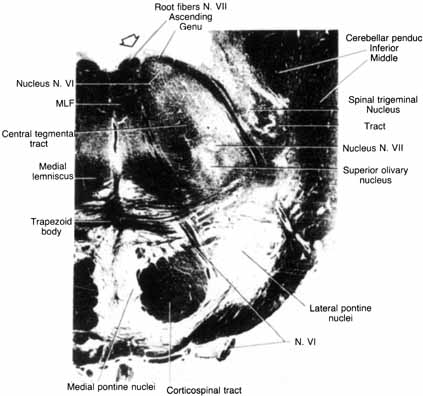

INTRAMEDULLARY SEGMENT

The motor nuclei of the sixth and seventh cranial nerves are initially in close proximity in the pontine subdivision of the metencephalon. As the metencephalon elongates and expands, the facial nucleus migrates ventrolaterally in relation to the abducens nucleus, displacing facial motor axons that loop dorsally in the floor of the fourth ventricle to form the facial colliculus (Fig. 1). This intimate relationship between the abducens and facial motor nuclei is the anatomic substrate for the clinical findings in congenital Möbius' syndrome and in acquired inflammatory, vascular, and neoplastic lesions that involve the intramedullary segment of the facial nerve.

Fig. 1 Cross section of pons, with relationships of facial motor nucleus (VII), abducens nucleus (VI), corticospinal tract, trigeminal nucleus, and tract. Facial colliculus (arrow). (Carpenter M: Core Text of Neuro-Anatomy. 3rd ed. Baltimore: Williams & Wilkins, 1985:152)

PONS

The facial motor nucleus contains about 7,000 motor nuclei 8 and is located in the ventrolateral angle of the lower pontine tegmentum (see Fig. 1). The facial nucleus can be divided into four separate cell groups that supply specific muscle groups: (1) dorsomedial (auricular and occipital muscles), (2) intermediate (frontalis, corrugator, and orbicularis oculi muscles), (3) ventromedial (platysma), and (4) lateral (buccinator and buccolabial).9 The motor axons exit the nucleus dorsally, loop around the abducens (VI) nucleus, and form the facial genu before emerging from the lateral aspect of the pons. The superior salivatory nucleus, which is located just rostral to the facial motor nucleus, is the origin of the parasympathetic fibers that supply the sublingual, submandibular, and lacrimal glands. These salivary and lacrimal fibers join the facial nerve as the nervus intermedius in the cerebellopontine angle.